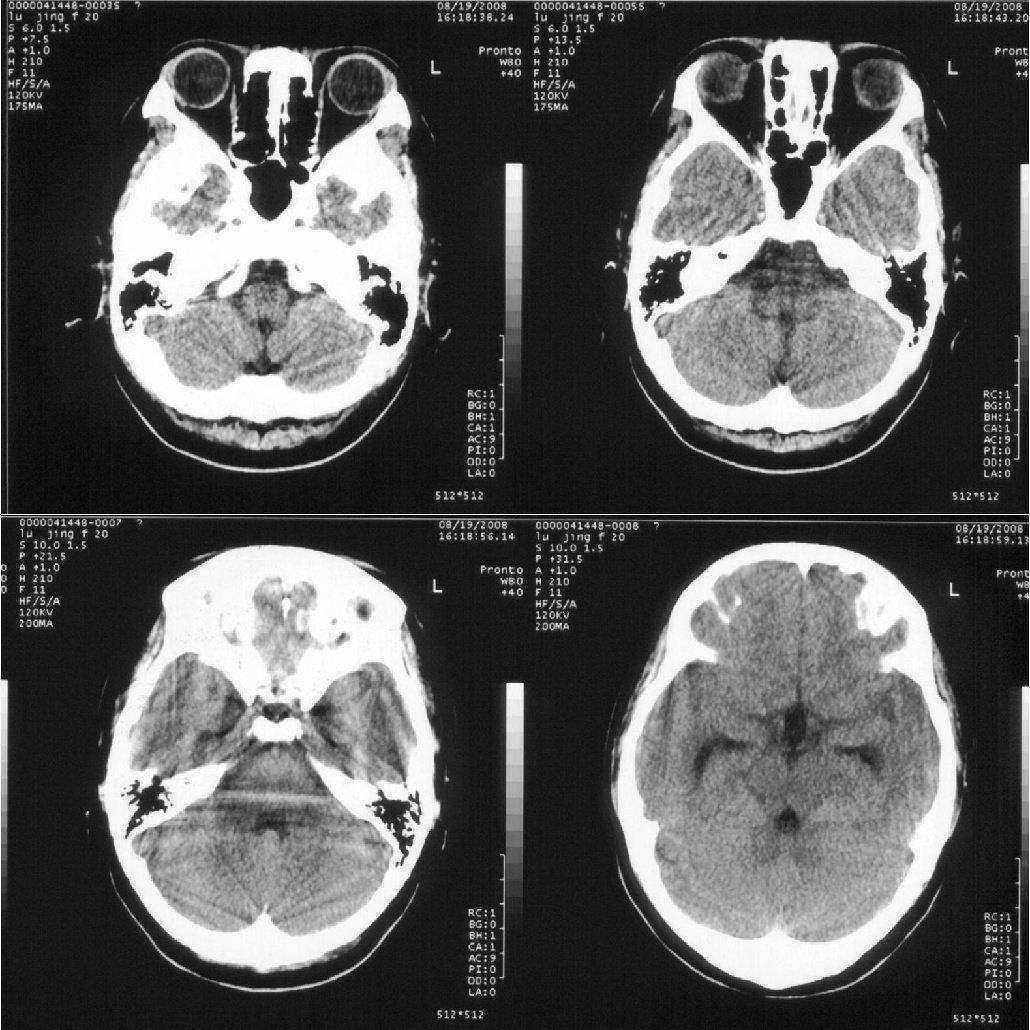

女,20岁。3天前突然恶心、呕吐,当时意识尚清楚。随后睡了一觉,醒后意识丧失,一直持续约5个小时左右才恢复意识。现在意识清楚,但一直干呕。

轻度脑积水,建议mr检查.

轻度脑积水,鞍上池有低密度占位,建议做核磁

双侧脑室及三脑室轻度增大,第四脑不大。考虑幂上脑积水,可能中脑导水管不完全阻塞可能。

追踪回访:脑压测定200,现在已经正常上学

脑室稍扩大,支持轻度脑积水诊断.

十楼的朋友说鞍上池有低密度占位,我认为那是扩大的三v.